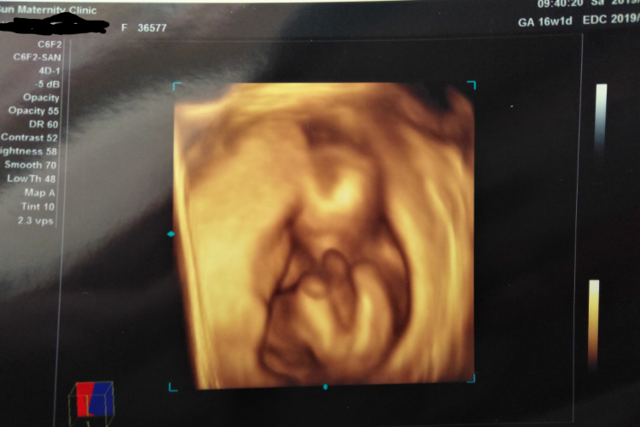

16週1日(16w1d・女の子)|maico888 さん(24歳)

エコー写真撮影時のエピソード:

はじめて4Dで見せてもらった時です。手を挙げて、ハーイって言ってるみたいです。まだ16週なのに、こんなにパーツがはっきりしてるんだと驚きました。

これ以降の4D写真では、なかなか顔が見えなくて、最初で最後のはっきり顔が見えるエコーです。旦那は、こんなにはっきり見えるんだ、こわーと言ってました。